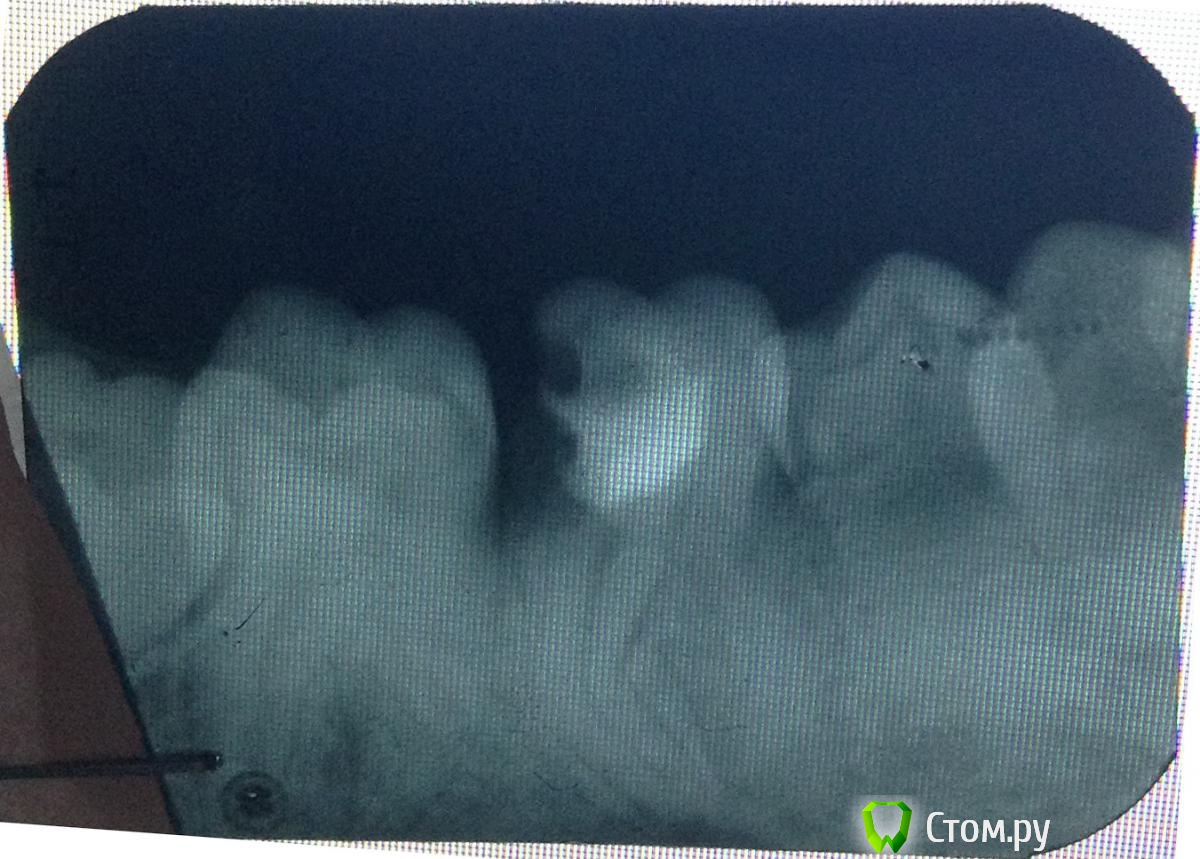

and13 Опубликовано 27 мая, 2014 Поделиться Опубликовано 27 мая, 2014 Приветствую. Ситуация такая: давно лечил зуб 36. Пломба и вроде каналы (не знаю точно насчет каналов, снимки прилагаю)Недавно откололось пломба, пошел к врачу. Она посмотрела снимки и сказала что тут ничего сделать нельзя совсем, зуб сгнил внутри якобы, только удаление зуба и ставить имплант. Направили к хирургу. Мне совсем не хочется удалять зуб. Вроде оставляют корни и ставят коронку или еще что? Посмотрите, выскажите свои предположения что можно сделать, жду любых советов. Спасибо п.с. качество фото может быть не очень, завтра могу приложить новые 1 Ссылка на комментарий

art700 Опубликовано 27 мая, 2014 Поделиться Опубликовано 27 мая, 2014 По снимкам зуб на удаление. А так снимки нужны получше Ссылка на комментарий

Scrabble Опубликовано 27 мая, 2014 Поделиться Опубликовано 27 мая, 2014 Дистально(сзади) зуб разрушен сильно-не восстановить. Ссылка на комментарий

and13 Опубликовано 27 мая, 2014 Автор Поделиться Опубликовано 27 мая, 2014 Сделал фото на фоне монитора. Вроде получше видно. П.с. делают же вроде коронку на штифт, чтобы не удалять зуб? Или может что-то еще подскажите?Корни то целые? Ссылка на комментарий